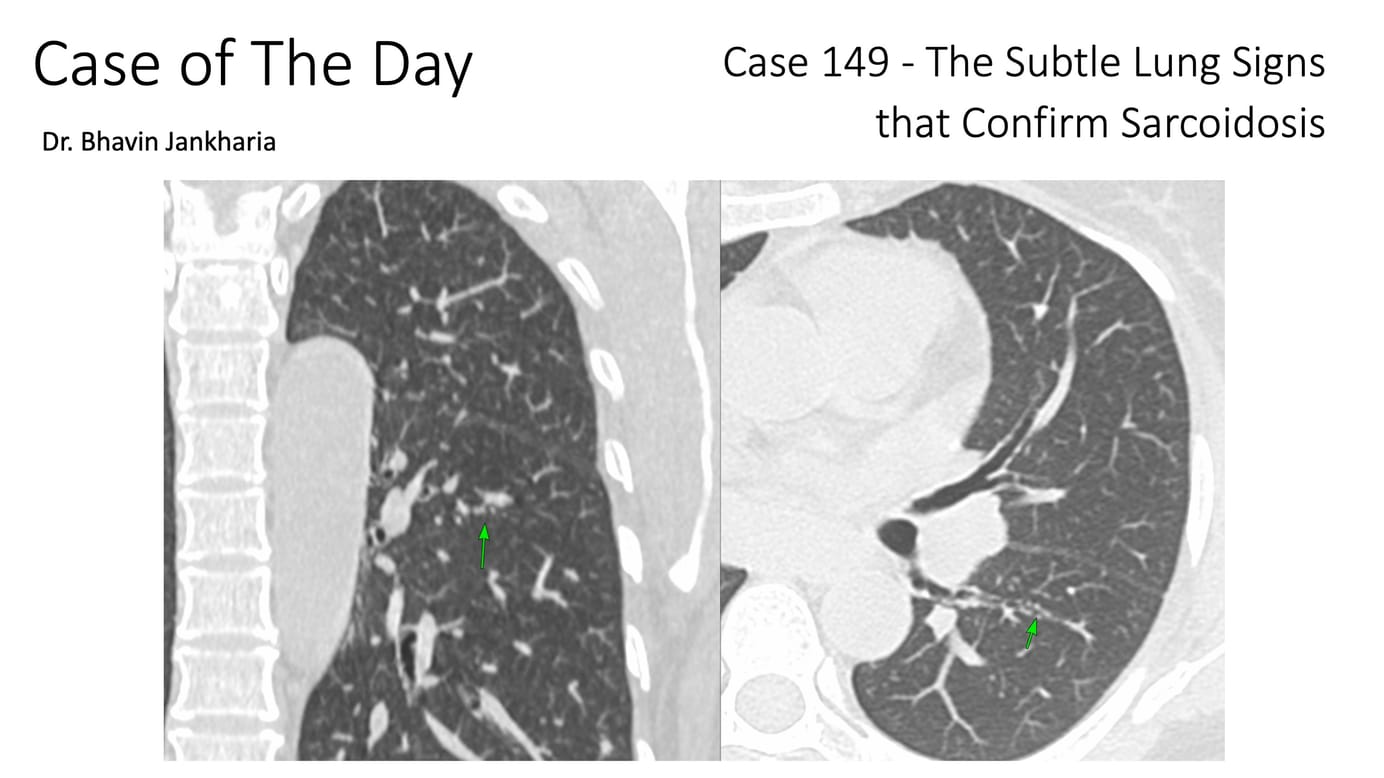

It is possible in many instances to differentiate between tuberculosis and sarcoidosis

This is a short 15 minutes lecture I delivered at a sarcoidosis meeting recently that describes the differences between tuberculosis and sarcoidosis. The lecture touches upon the different nodal and lung presentations and how even healed disease differs. In indeterminate cases, biopsy is usually the best option.